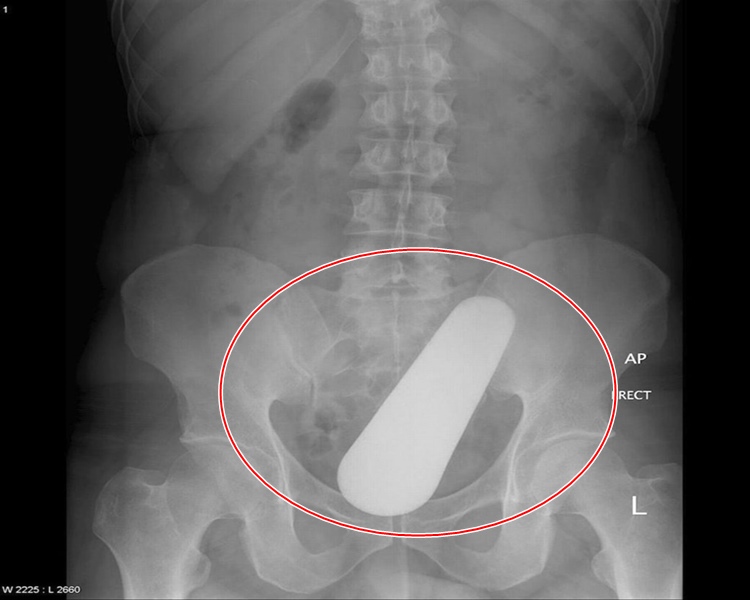

Um pilão introduzido na região íntima